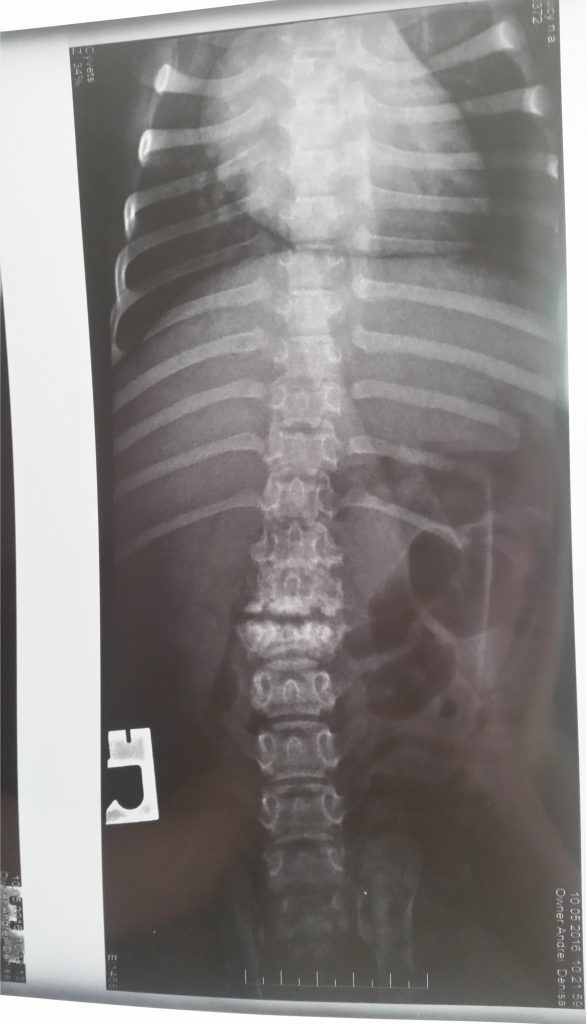

Va atașez radiografia .

Am sa va trimit câteva filmulețe cu cãțelușa, poate chiar astãzi. Mãduva nu a fost afectata, doar nervii periferici. Când am luat-o am fost la mai multi doctori, unii chiar cu renume, care mi-au recomandat eutanasierea ei, spunând ca nu au ce sã-i facã. Îmi spuneau ca e pãcat sa se chinuie și ea, și eu. As dori acum sa le arat acestor doctori cum este ea acum. Am multe radiografii. Aveți cumva site în limba engleza ? Ar fi mai ușor sã-i dau doctorului sa citeascã mai multe.